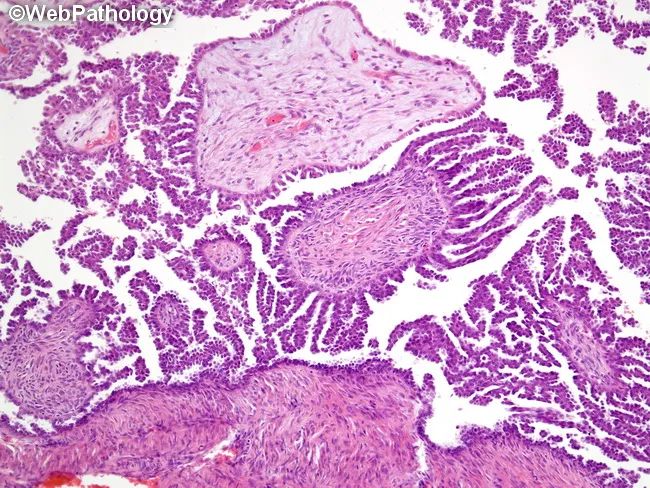

(形态)微乳头直接从大乳头直接发出(乳头直接分支,而非逐级分支)[特征] 微乳头轴心纤细,长:宽5:1 (细长的指状乳头)[特征]

(细胞)肿瘤细胞形态更加均匀一致[特征] ,(不同于经典型SBT的细胞异质性)常缺乏纤毛细胞或嗜酸性细胞,核圆,胞质稀少,可见明显小核仁,核异型性轻-中度 (超过经典型SBT)[特征],核分裂像少见(超过经典型SBT)